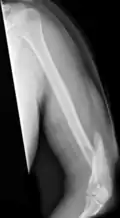

A transverse fracture of the humerus shaft -

A spiral fracture of the distal one-third of the humerus shaft -